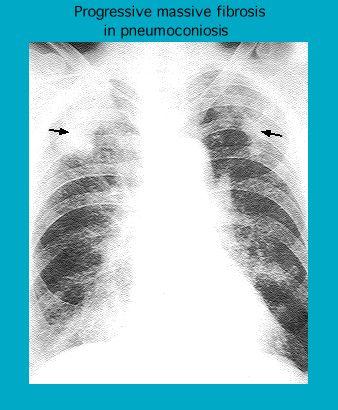

Radiograph showing progressive massive fibrosis